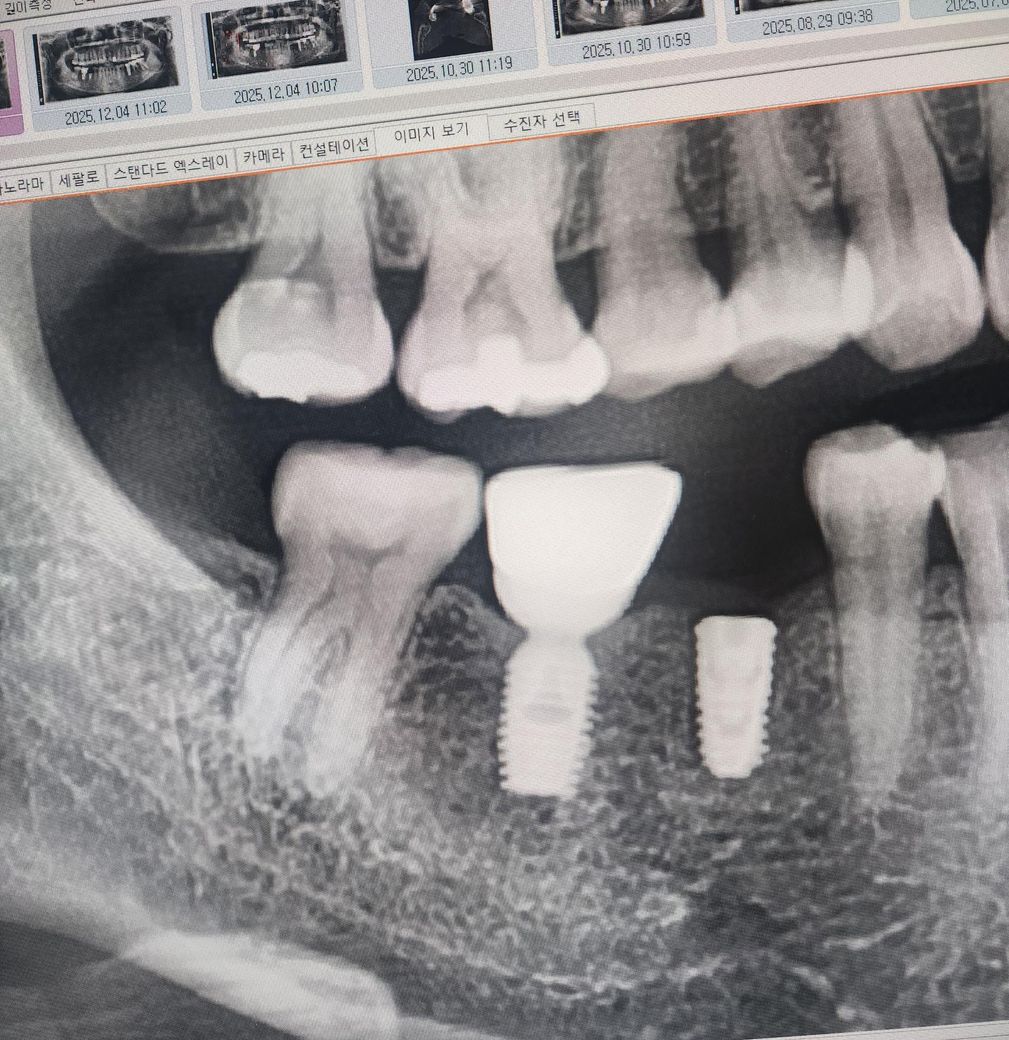

엑스레이상으로 보시기에 염증이나 뼈가녹은거같은건 없어보이시나요?

일단 뒤에 있는 임플란트 자체에는 문제가 없어 보입니다. 다만 오래되다 보니 뒤쪽에 있는 치아 부분이 뒤로 밀리면서 공간이 많이 생긴 것으로 보입니다. 치실이 그냥 통과할 것으로 보이며 이러한 경우에는 음식물을 섭취하더라도 해당 부분에 음식물이 많이 고여 잇몸에 부분적으로 통증이 나타날 것으로 보입니다. 임플란트 자체에는 문제가 없으며 꼭 픽스쳐를 제거하고 재식립할 필요는 없습니다.

1. 엑스레이상 픽스쳐 상태는 굉장히 양호합니다. 굳이 교체할 필요 없고, 호환되는 종류면 그냥 위에 보철만 새로 하시면 됩니다.

2. 음식물 잘 끼는 건 주로 보철 문제입니다. 크라운 스플린트로 이어서 제작하시면 될 것 같습니다.